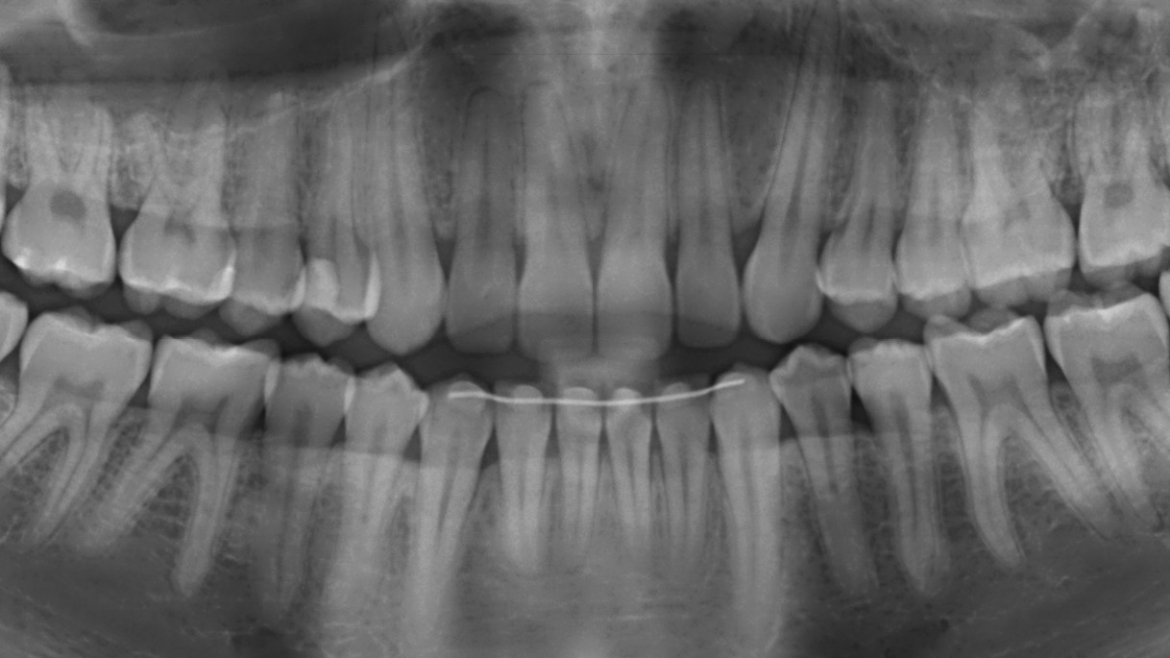

A Radiografia Panorâmica é uma técnica radiográfica que permite ao dentista a visualização das arcadas dentárias superior e inferior em um único filme. Além da visualização geral de todos os dentes, permite também a observação das estruturas anatômicas de maxila e mandíbula.